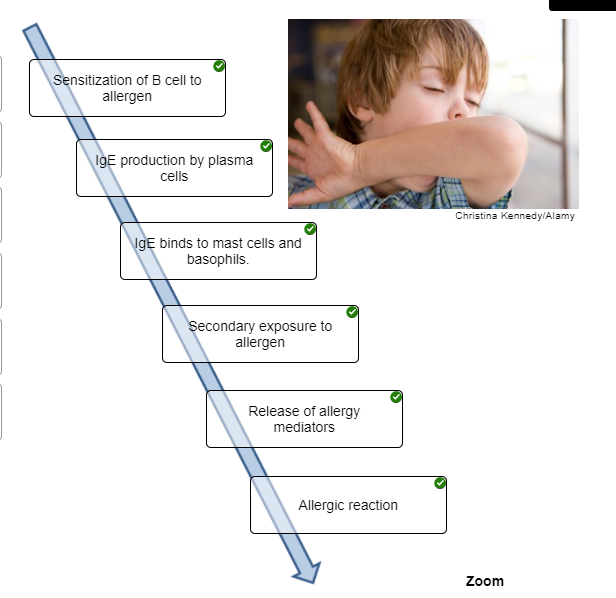

Put the steps that occur during an immediate-reaction allergic response in the correct order.

Place the steps that occur during an immediate-reaction allergic response in the correct order.

1. Indicate the order of cell types involved in the response to the

first exposure to an allergen.

2. Antibodies attach to mast cells

via what part of the antibody structure?

3. With second exposure

to an antigen, the antigen molecules bind to __________.

1. Antigen-presenting cell, helper T cell, B cell, plasma

cell

2. Constant region

3. IgE on the mast cells